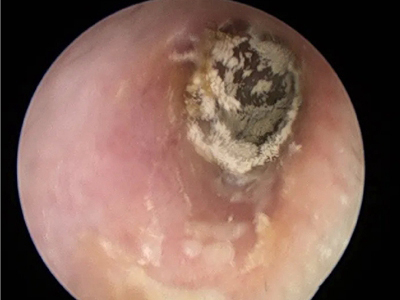

霉菌性外耳道炎耳朵里有黄色粉末物图

霉菌性外耳道炎皮损为厚厚的白色鳞屑,并且向深处扩展,看上去像云雾状,部分相互融合成大块状,表面粗糙不平,中间有少许正常黏膜。